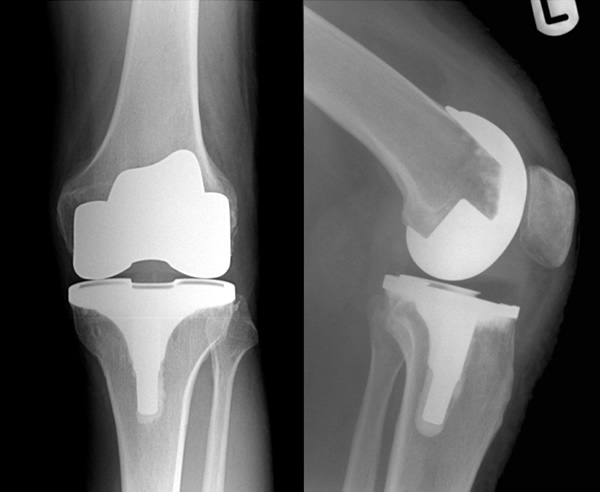

The company ORTHOPEDIC NIKIFOROV was founded in 1998 by the candidate of medical sciences. doctor of orthopedic-traumatologist of the highest category Nikiforov IA Owing to high professionalism and results of work, ORTONIC has gained well-deserved reputation and reputation among colleagues and population of Dnepropetrovsk region and CIS countries (Russia, Moldova, Armenia, etc.). The principle of the enterprise is NO IMPOSSIBLE, it is based on knowledge, experience and active implementation of modern technologies in orthopedics and traumatology. Conservative methods of treatment include individual selection of medicines, therapeutic blockades, manual therapy, massage, physiotherapy (vibration table, magnetotherapy, bioptron, electromyostimulation, etc.), rehabilitation with the suggestion of the necessary concomitant devices and means for the fastest recovery (corsets, bandages, various joint fixators, crutches, walking sticks, etc.). Various minor invasive interventions (chymonucleolysis, vertebroplasty, kyphoplasty, percutaneous nucleoplasty using cold plasma) that are performed on an outpatient basis are successfully used to treat problems associated with spine pathology. The latest modern treatment methods introduced in our company are endoscopic operations using the TYSSES technique of Joimax (Germany) with intervertebral hernias, stenosis and other pathologies of the spine, which allow to avoid complications occurring during open operations and the accompanying general anesthesia. We have many years of successful experience in traditional and modern minimally invasive endoprosthetics of large and small joints, which remains the main direction of our activity. Our company is the exclusive representative of the German company IO International Orthopaedics Holding GmbH, which based on the already known prostheses, its ideas and technological capabilities, has developed and implemented a new concept in hip replacement - an artificial joint prosthesis (ICON). We assist interested colleagues in training the operative technique for installing an artificial joint prosthesis - ICON, both in the workplace and in Germany. For 20 years we have been successfully cooperating with Sanitatshaus Gerd Klinz ortho team, an enterprise that for 20 years has been one of the leading places in Germany for the production of functional prostheses of the upper and lower limbs, as well as cosmetic prostheses of limbs and other body parts (nose, ears, eyeballs, fingers). We have an atmosphere of friendliness and human participation. Politeness, benevolence, the desire to understand and help is the basis of our attitude towards patients. We are always glad to see you and will do our best to make you feel great! We are waiting for you at: Ukraine, Dnepr, Gagarin Ave., 13 (under reconstruction) on all questions to address: tel .: +38 (050) 488-88-92 E-mail: orthonik.ukr@gmail.com Germany, Spine Nano Klinik, Zeppelinstr. 21, Potsdam Tel. +4901801121919 E-mail: kmw.nikiforov@hotmail.de